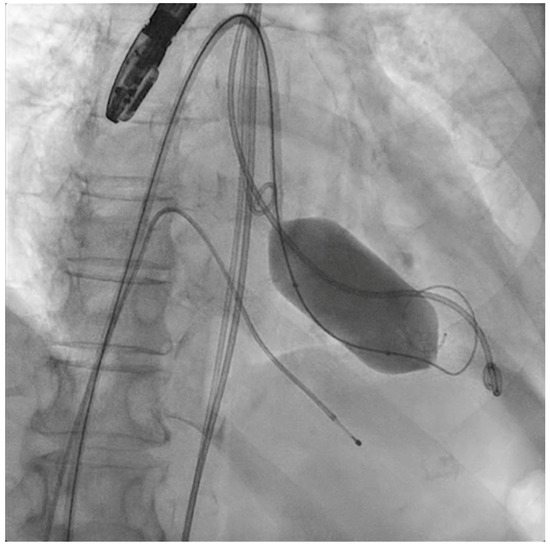

The next steps consist of crossing the mitral valve with three long high-support 0.014´´ wires downstream into the left ventricle (LV) (Figure 2) and then advancing three lithotripsy balloons (Shockwave Medical) across the mitral valve; with rapid pacing (120 beats/min), simultaneous inflations of all balloons will deliver a total of 90 pulses from each balloon (Figure 3). Finally, access to the LV has to be attained again with the Safari wire to complete PMC with large balloons appropriately sized to the mitral valve area and diameters (Figure 4). Embolic protection devices are encouraged to avoid neurological or systemic ischemic events due to calcific debris.

Figure 3.

Simultaneous inflation of three 7 × 60 mm shockwave balloons on the mitral valve for lithotripsy applications.